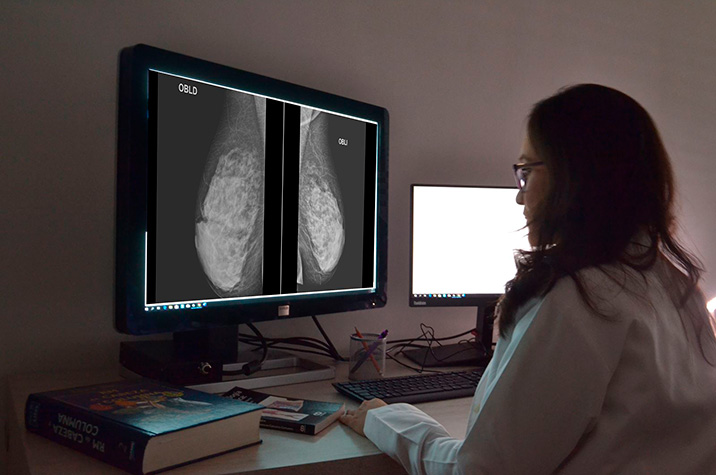

Participación en el primer rastreo mediante mamografía e incidencia y mortalidad por cáncer de mama en los 25 años siguientes

25 septiembre 2025

Este estudio demuestra que las mujeres que no participan en la primera detección representan un grupo importante con riesgo elevado de morir por cáncer de mama a largo plazo, lo que justifica la implementación de intervenciones específicas para mejorar la adherencia a las pruebas de detección y, así, reducir el riesgo de mortalidad. El aumento de mortalidad luego de 25 años de seguimiento fue del orden de 2 casos cada 1.000 participantes. BMJ, 24 de septiembre de 2025.